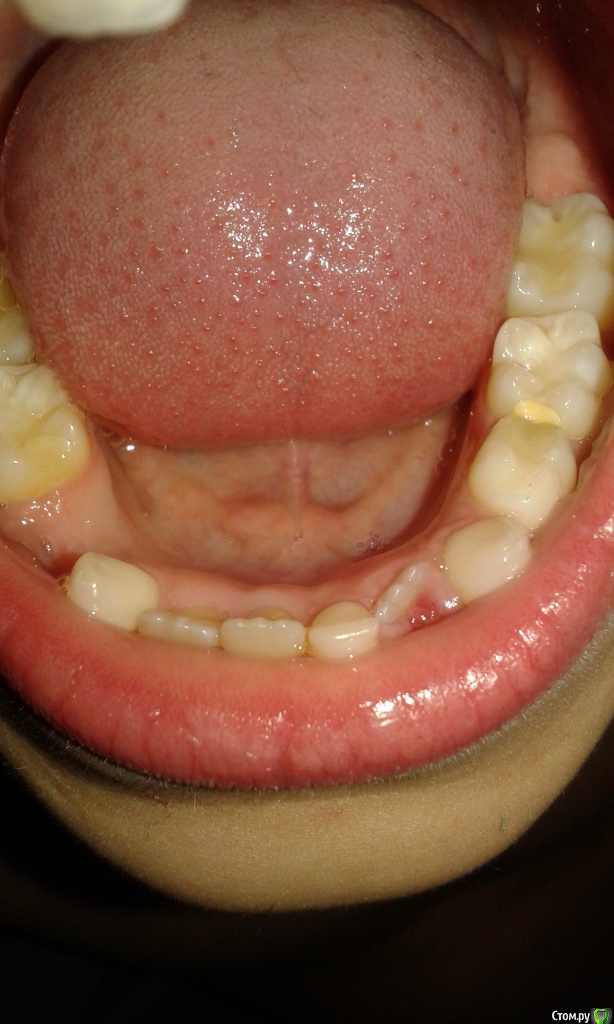

На сегодня ребенку 7 лет и у него вылезли все три коренных нижних зуба, но остался еще один нижний молочный зуб в этом ряду.

Вопрос состоит в том, что делать с этим молочным нижним зубом.